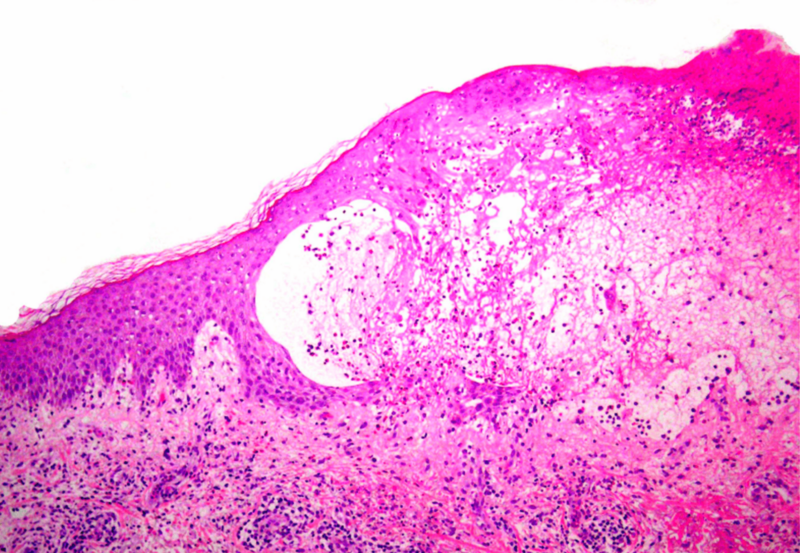

pemphigus_vulgaris_-_low_mag

• Pemphiguserkrankungen

Wie diese Autoimmundermatose heutzutage gemanagt werden kann

Blasenbildende Autoimmundermatosen der Haut zählen zu den seltenen Erkrankungen und verlaufen unbehandelt häufig tödlich. Durch eine intensive Therapie können Prognose und Lebensqualität der Betroffenen deutlich verbessert werden. Wie eine kürzlich...…

pemphigoid

• Bullöse Autoimmundermatosen

Worauf bei der Diagnose der BAID geachtet werden muss

Blasenbildende Autoimmundermatosen (BAID) sind eine Gruppe seltener, potenziell lebensbedrohlicher Erkrankungen, die klinisch durch Läsionen an Haut oder Schleimhäuten in Erscheinung treten, welche jedoch entgegen der Intuition nicht immer mit Blasenbildung...…

• Autoimmunbullöse Dermatosen

Autoantikörper greifen Integrität der Haut an

Bullöse Autoimmundermatosen stellen eine heterogene ­Gruppe von seltenen, teils schweren Autoimmunerkrankungen dar, zu welchen die Pemphigus- und Pemphigoid-Erkrankun­gen, die Epidermolysis bullosa acquisita und die Dermatitis herpetiformis Duhring zählen. Gemeinsames Charakteristikum...…